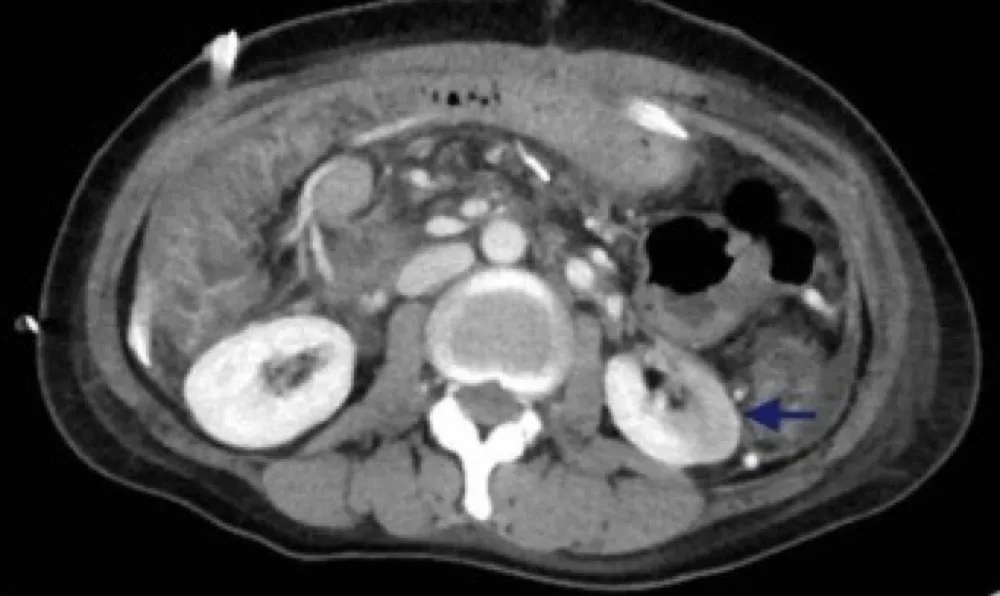

Uma causa incomum de hematúria glomerular intermitente!

Hematúria pós infecção, caso clínicos para auxiliar no entendimento de causas glomerulares comuns e raras...